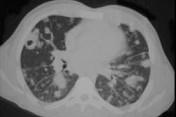

问题 男,32岁,咳嗽,咳脓痰伴发热、胸痛一月余,抗感染治疗不见好转,PPD(-),结合CT图像,最可能的诊断是 ( )

选项 A.肺炎 B.肺结核 C.肺脓肿 D.肺癌 E.肺放射菌病

答案 E